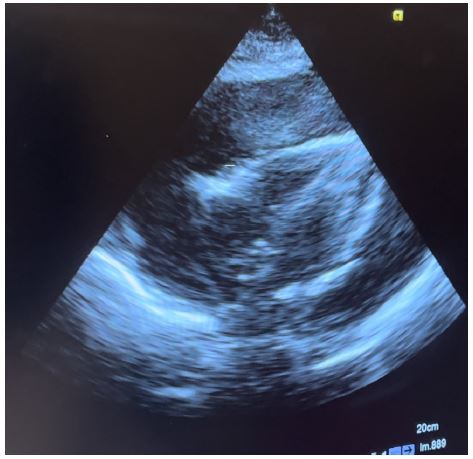

Figure 1: Subcostal echo view showing massive pericardial effusion.

Figure 2: Apical 4 chamber echo view showing massive pericardial effusion with compression of the right side of the heart.

Transthoracic echocardiography is the best diagnostic imaging, useful in diagnosis and management of tuberculous pericardial effusion. Echocardiography can provide an estimate of the size of effusions. Generally, the size of the effusion on echocardiography indicates the volume of pericardial fluid as follows: small (<10 mm), which corresponds to 50-100 mL pericardial fluid; moderate (10-20 mm), corresponding to 100 - 500 mL pericardial fluid and large (>20 mm), corresponding to >500 mL pericardial fluid [19] . The study of Diakité et al. showed 18% of moderate abundance and 81% of high abundance among 49 cases of tuberculous pericarditis [6].